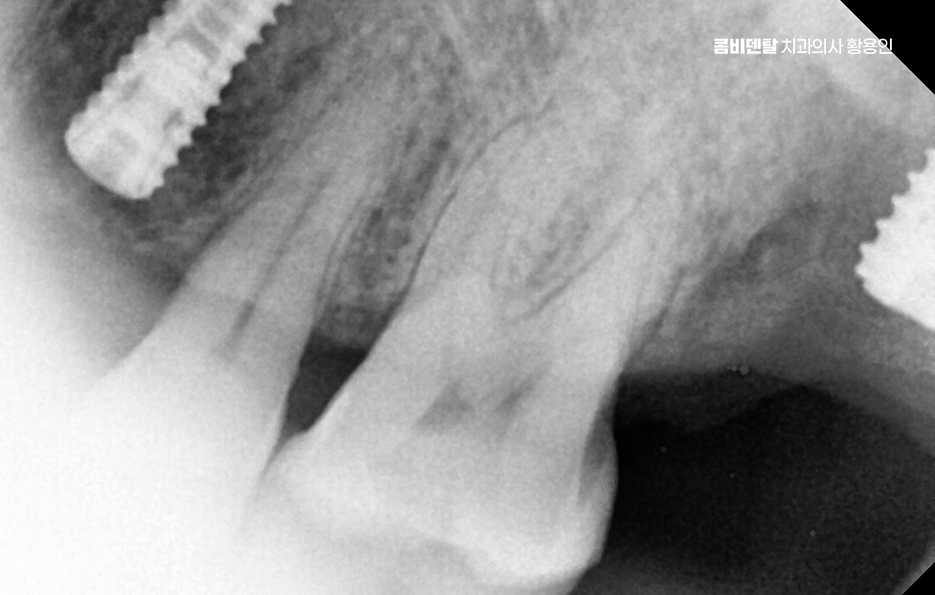

어금니는 단순히 음식을 씹는 역할만 하는 게 아니며 우리 턱과 얼굴을 지탱해주는 일종의 기둥 같은 존재로서 특히 아래 어금니는 턱뼈에 직접 연결되어 있어서 이 부분이 빠지면 턱뼈 자체가 빠르게 흡수되기 시작하고 뼈는 자극이 있어야 유지되는데 어금니가 없어진 자리엔 씹는 자극이 사라지니까 뼈가 점점 가라앉는 거예요.

더 심각한 건 치열 전체가 무너지는 것으로 어금니가 빠지고 그 자리를 비워 두면, 위에 맞물리는 치아가 점점 내려오거나, 옆 치아가 쓰러져 들어가며 이렇게 정출된 치아는 다시 제자리로 돌아오지 않기 때문에, 나중에 임플란트를 하려고 해도 공간이 맞지 않아서 교정치료를 먼저 해야 할 수도 있었어요.

그래서 이런 문제들을 막기 위해서라도 임플란트는 어금니 상실 후 중요한 치료 옵션으로서 임플란트는 빠진 치아의 뿌리 역할까지 해주기 때문에, 단순히 공간을 채우는 게 아니라 턱뼈에 자극을 줘서 뼈 흡수를 막아주고, 위아래 치아가 정상적으로 맞물릴 수 있게 해주며 다른 보철 방식과 비교해도 장기적인 안정성과 기능 회복 면에서 유리한 거예요.

임플란트를 빨리 하는 게 좋은 이유는, 시간이 지나면서 턱뼈가 점점 흡수돼버리면 임플란트를 심을 뼈 자체가 부족해지는 상황이 생기기 때문이며 이때는 뼈이식이나 상악동 거상술 같은 추가 수술이 필요하게 되고, 치료 기간도 길어지고, 비용도 많이 올라가기 때문에 어금니가 빠졌다고 방치하는 시간만큼 치료는 더 복잡해질 수 있다는 점에서 어금니 없으면 얼굴 발음 및 오늘 알아본 것처럼 다양한 문제로 이어질 수 있음을 잘 이해하여 빠르고 나에게 맞는 치료 계획을 세우시고 장기적으로는 수명 유지까지 잘 고려하여 치료 계획을 잘 세워보시길 바라고 있어요